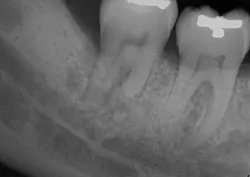

A clinical periodontal and radiographic assessment is completed. Although there is moderate bone loss in all four quadrants, his periodontal status is stable with the exceptions of Nos. 18 and 31 distal (figures 1 and 2). Both areas reveal direct distal probing depths of at least 10 mm and radiographic infrabony distal defects.

Figure 1: No. 18

Many periodontists find these defects very predictable to treat with surgery and bone regenerative materials. The high peak of remaining bone provides support, blood supply, and biologic assistance to the grafted area. Conversely, this area tends to be very difficult to treat nonsurgically. Accessing the direct distal of these teeth is extremely challenging, and at depths beyond 5–6 mm, the results of the nonsurgical approach are expected to be poor.